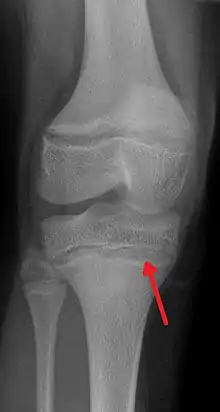

La marque du cartilage épiphysaire reste visible sous forme d'une ligne épiphysaire.

En cas de saturnisme chronique et important, apparait sur les radiographie osseuses d'os longs une ligne blanche parfois dite métaphyséale. Elle se forme aux environs de la zone de production du cartilage[1]. ce phénomène a notamment été décrit en 1933 par Vogt[2] puis par Park & al. [3]